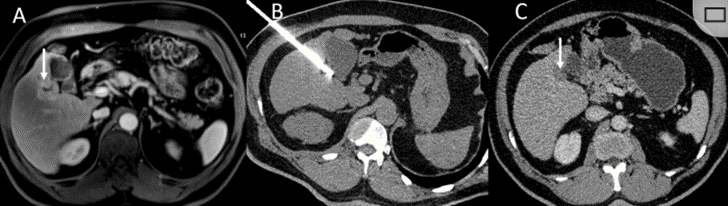

冷凍消融膽囊附近腫瘤病灶

(A)動(dòng)脈期 MRI 顯示膽囊附近有外周增強病變(箭頭)。

(B)手術(shù)過(guò)程中 CT 顯示冷凍探針位于病灶內。

(C)消融后,術(shù)后 1 個(gè)月CT 顯示完全消融(箭頭)。